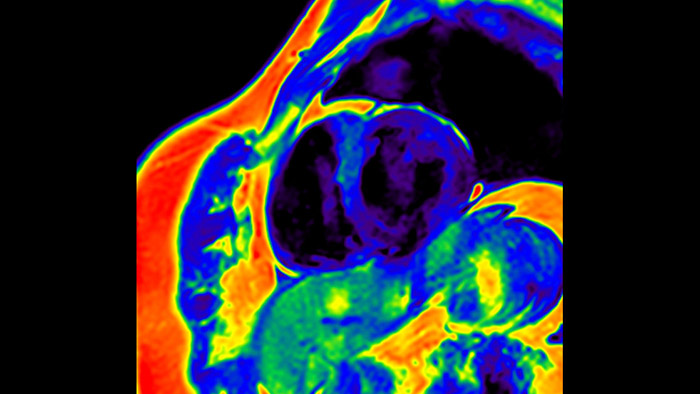

Quantify Myocardial Strain

IntelliSpace Portal MR Caas5,6 Strain7 assists in patient diagnosis and monitoring by providing global strain parameters such as global longitudinal strain (GLS), global circumferential strain (GCS), and global radial strain (GRS), using short and long axis MR images, as well as describing the myocardium deformation- such as shortening, thickening, and lengthening during the cardiac cycle.